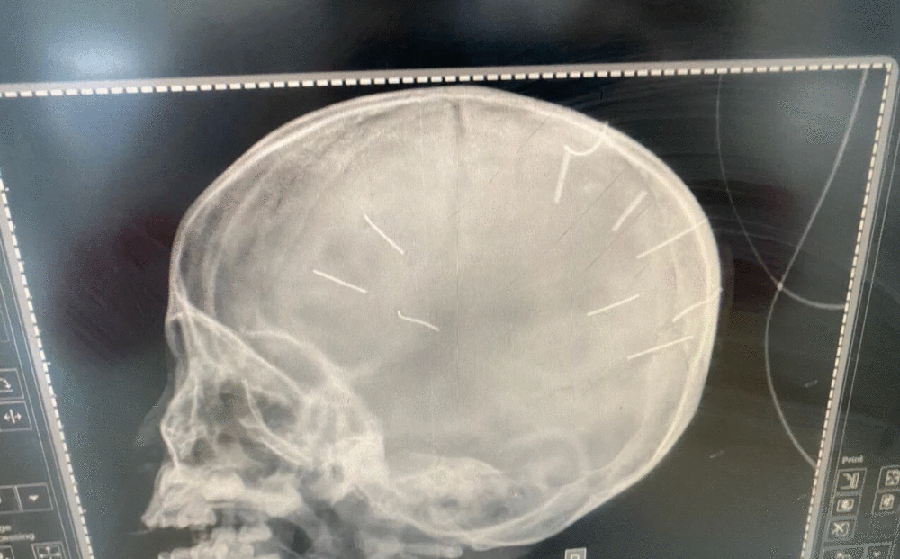

Theo đó, sáng ngày 17-1, khi chị L đi làm, Huyên hỏi nhưng không thấy cháu A trả lời, bị can tát và dùng đinh ghim vào vùng đầu cháu bé. Sau khi thực hiện hành vi trên, Huyên đưa cháu A tới nhà chị KTH - người được Huyên và chị L nhờ trông cháu A.

Đáng chú ý, Huyên còn khai nhận, trước đó còn có nhiều lần bạo hành, ngược đãi cháu bé bằng nhiều thủ đoạn khác nhau như: Cho uống thuốc trừ sâu, cho nuốt đinh ốc vít, đánh gãy tay khiến cháu bé phải nhập viện để điều trị.